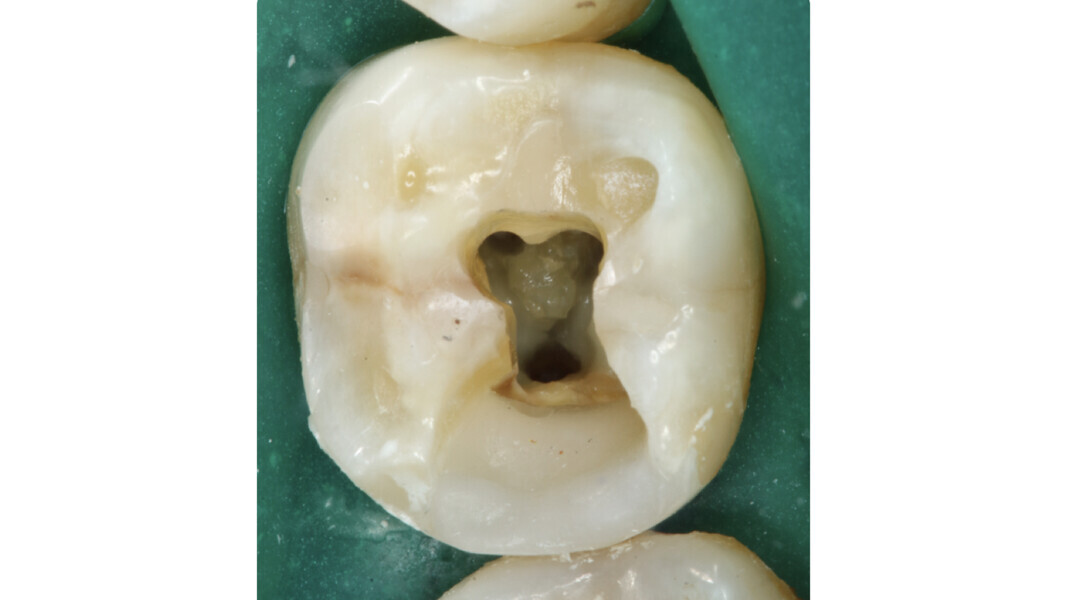

Fig. 2: Image of the access cavity prepared, showing excess removal of healthy tissue in the mesiobuccal and apical direction.

An inadequate access cavity in terms of position, depth and extension can lead to complications in the subsequent phases, making it impossible to locate the canal orifices, overstressing the mechanical nickel–titanium (NiTi) files or weakening the residual dental structure (Figs. 1–5). While, in the past, there was a tendency to emphasise the importance of a large access cavity that would allow the insertion of manual and mechanical instruments following the main axis of the canal, in recent years, the proposal of minimal access cavities defined in various ways (“ultra-conservative cavity”, “ninja cavity”, “truss access cavity”)4 has become predominant.